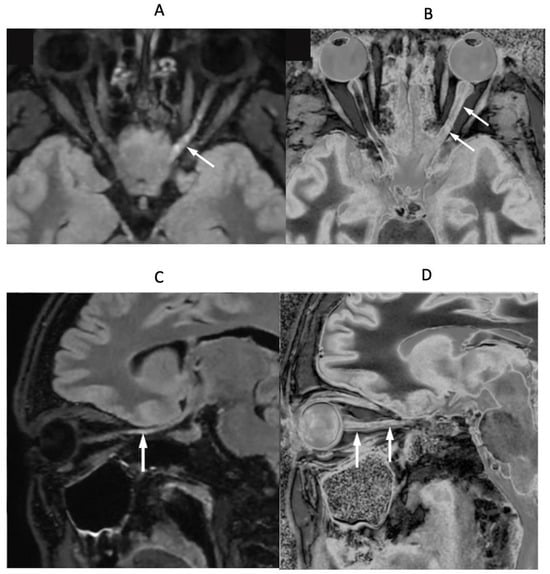

Figure 11 shows narrow mD dSIR images in a normal adult control (Figure 11A) and in a 77-year-old patient with MS (Figure 11B) during a relapse. In addition to the whiteout sign, there is a loss of contrast between gray and white matter in the thalamus of the patient (Figure 11B). Also, the heads of the caudate nuclei, as well as the insular and peripheral cortices, appear isointense with CSF on the dSIR image. These are grayout signs. No evidence of a whiteout sign or grayout signs was seen on the corresponding T2-FLAIR images.

Figure 11.

Skull-stripped images of a normal control (A) and 77-year-old patient with MS during a relapse (B). There is low signal in the normal white matter in (A) and a whiteout sign in (B). In addition, the gray matter in the thalamus and cortex has a uniform low signal and is nearly isointense with CSF. These are grayout signs. No evidence of a whiteout sign or grayout signs was seen on the positionally matched T2-FLAIR images.

In a patient with optic neuritis and suspected MS, Figure 17A,B (upper row) show axial fat saturated T2-FLAIR (Figure 17A) and narrow mD dSIR (Figure 17B) images of their optic nerves. Figure 17C,D (lower row) show parasagittal oblique fat saturated T2-FLAIR (Figure 17C) and narrow mD dSIR (Figure 17D) images of the left optic nerve. The right optic nerve appears normal in Figure 17A,B. The left optic nerve shows a distal abnormality on the T2-FLAIR axial and parasagittal images (white arrows), but shows proximal and distal abnormalities on the corresponding dSIR images (white arrows).

Figure 17.

Patient with optic neuritis and suspected MS. The upper row shows axial fat saturated T2-FLAIR (A) and narrow mD dSIR (B) images. The lower row shows matched oblique fat saturated T2-FLAIR (C) and narrow mD dSIR (D) images through the left optic nerve. Distal changes are seen in the left optic nerve on the T2-FLAIR images (arrows) but both proximal and distal changes are seen in the left optic nerve on the dSIR images (arrows).